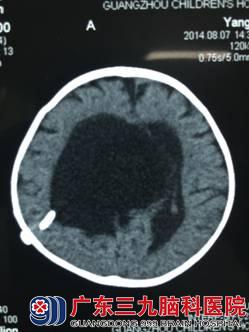

患儿洋洋(化名),女, 8个月时仍不能抬头、翻身等,到外当地医院检查头部CT,显示:小脑上池蛛网膜囊肿合并脑积水,医生为其行脑室腹腔引流术,术后1个月复查头部CT显示脑室缩小,但原蛛网膜囊肿仍继续增大,压迫了脑干。

头部CT可见脑室扩张明显,分流管位于脑室内,蛛网膜囊肿增大,压迫脑组织。